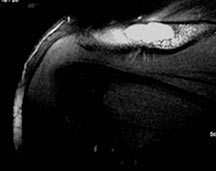

- Humerus

- Radiographically variable appearance: may appear benign (geographic) or malignant (permeative or moth eaten)